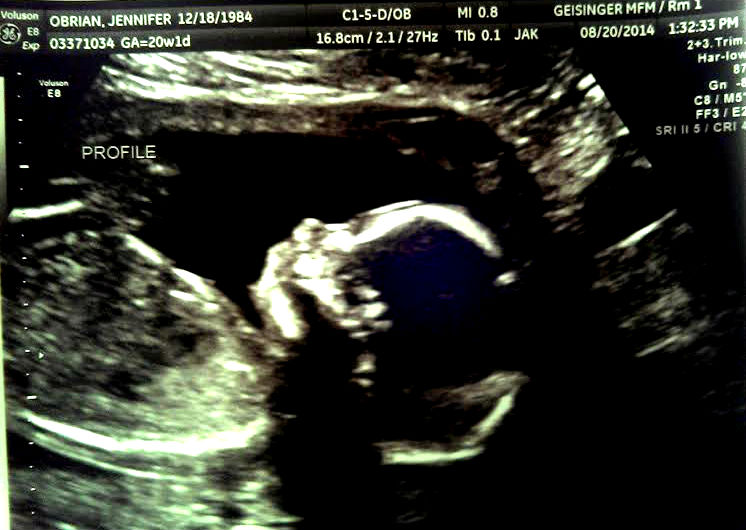

I'm 21 weeks tomorrow, and at our 20 week anatomy scan we learned we are having a little girl!!

We were ecstatic! She's right on target for her size and weight, and she's head down.

She just looks so perfect already, and she's so very active!